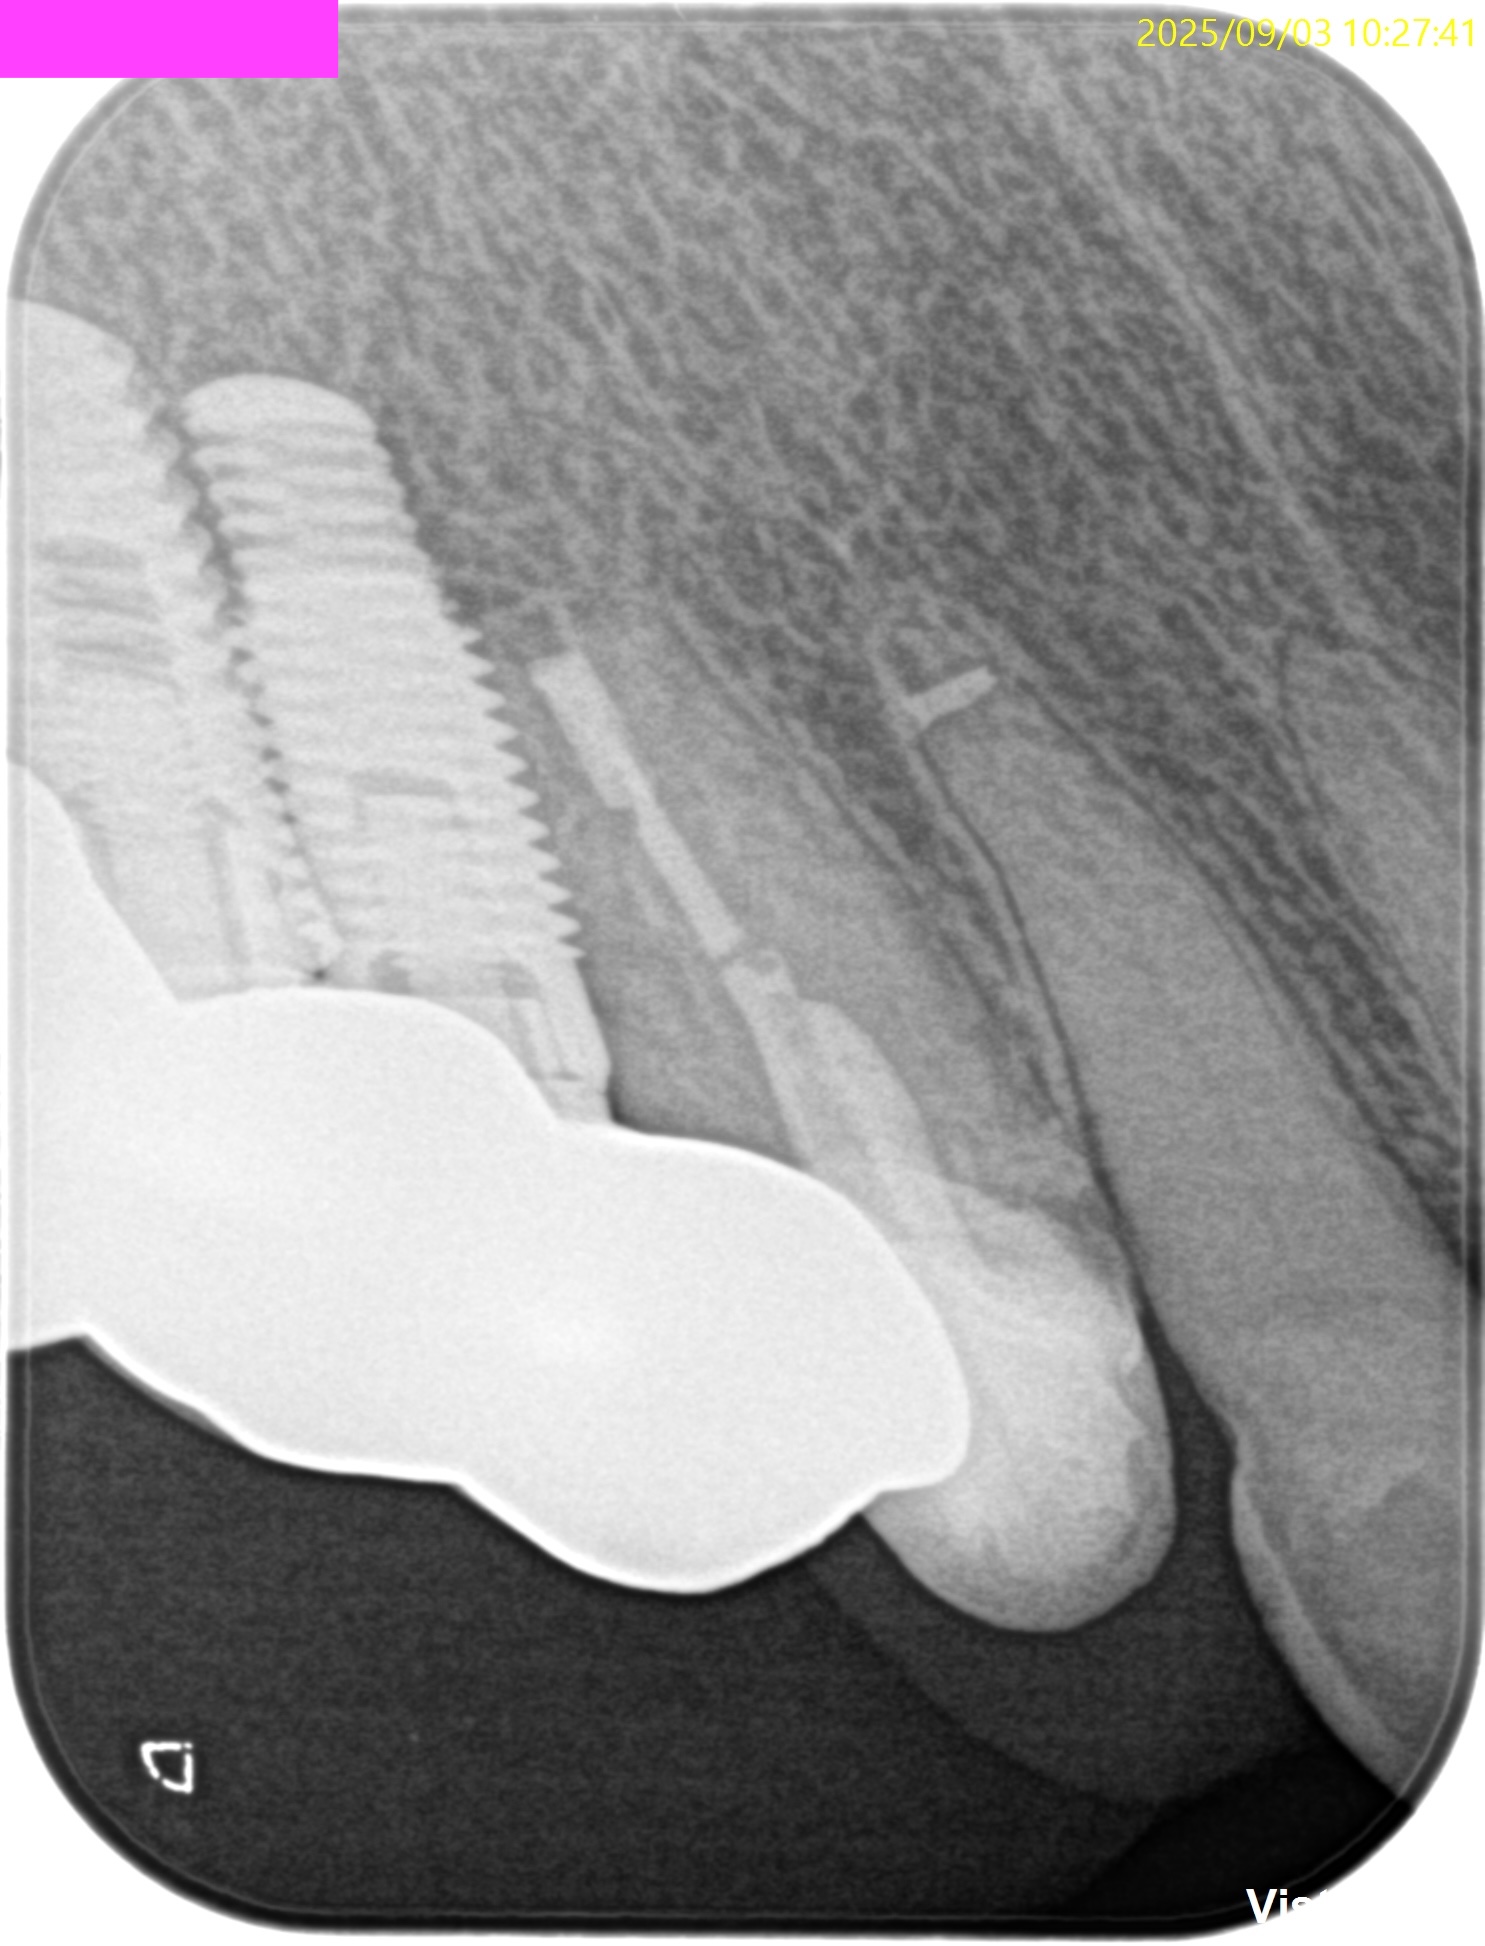

#6 Apicoectomy 10M recall(2025.9.3)

術直後と比較した。

90%がた治癒していると言えるだろう。

Gutta Percha Pointは除去できていないまま、なのにだ。